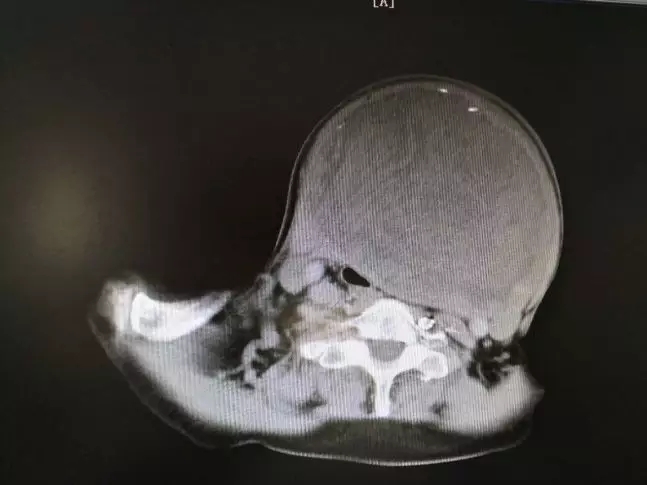

陈XX入院时见颈前肿物直径已达20cm,进一步行CT检查后,提示颈部肿块巨大,已经将喉压向一边,同时压迫气管、周围血管、神经,气管最狭窄处直径约5-6mm;病人年龄大,同时伴有双肺炎症改变,脑梗塞、冠心病,且耳聋、智力有一定障碍,沟通困难。